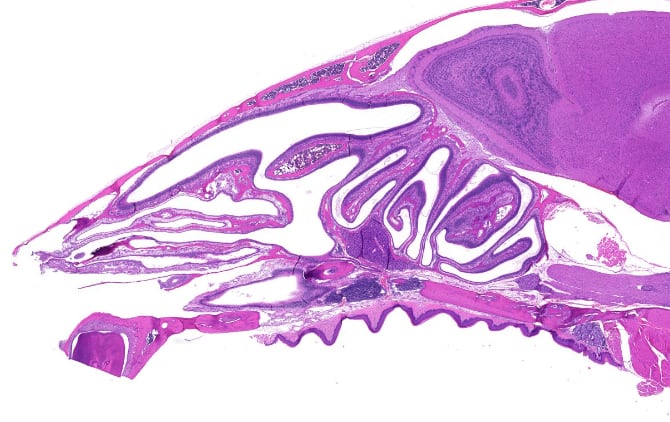

La nariz es una de las principales vías de acceso a nuestro cuerpo: el aire que respiramos, los aromas que olemos y los microbios que nos enferman. En su camino hacia adentro, el aire pasa por los cornetes nasales, las placas óseas largas, estrechas y curvadas que parecen una concha y sobresalen hacia el conducto respiratorio. Los cornetes están cubiertos por un tipo de tejido único que secreta moco y contiene muchas ramas de células nerviosas que son responsables de nuestro sentido del olfato. La estructura y función de los cornetes permite que el aire se caliente y absorba humedad antes de llegar a los pulmones.

Los cornetes nasales no solo son el principal punto de entrada de patógenos a las vías respiratorias, sino que también tienen un punto débil importante: como están situados tan cerca del cerebro, no son accesibles a los anticuerpos que nuestro sistema inmunitario envía a través del torrente sanguíneo durante una infección de las vías respiratorias superiores.

“Nos sorprendió descubrir las células B en los cornetes nasales, tejido óseo que no se sabía que apoyara una respuesta inmunitaria mediada por anticuerpos. Esta reubicación en el tejido óseo es similar a lo que ocurre en la médula ósea, y es posible que este entorno de nicho tenga otras funciones más allá del mecanismo inmunitario que identificamos”.

Los nuevos hallazgos muestran que las células secretoras de anticuerpos se trasladan desde los ganglios linfáticos nasales a las glándulas productoras de moco en los cornetes nasales, justo debajo de sus capas externas de células, y que secretan sus anticuerpos en estas glándulas. Esta defensa inmunitaria compensa la incapacidad de los anticuerpos sanguíneos para llegar a esta puerta de entrada a través del torrente sanguíneo y es importante no solo en el contexto de virus y otras enfermedades: también protege el cerebro y las numerosas terminaciones nerviosas de esa parte del cuerpo, responsables de nuestro sentido del olfato.